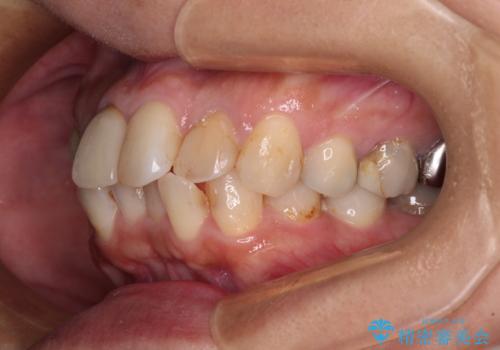

【モニター】処置歯の多い歯列 インビザラインでデコボコを整える

- 上下前歯のデコボコを気にして来院された患者様です。

歯列としては、ワイヤー装置でもインビザラインでも、どちらでも対応可能でしたが、処置されている歯が多く、ワイヤー装置を装着するためには処置歯のやり直しが必要な状態でした。

インビザラインでもアタッチメントを装着できないという同様のデメリットがありますが、比較的矯正治療を行いやすい歯列であったので、インビザラインによる矯正治療を行うこととしました。

術中や仕上がりに特に大きなトラブルはなく、スムーズに治療を終えることができました。